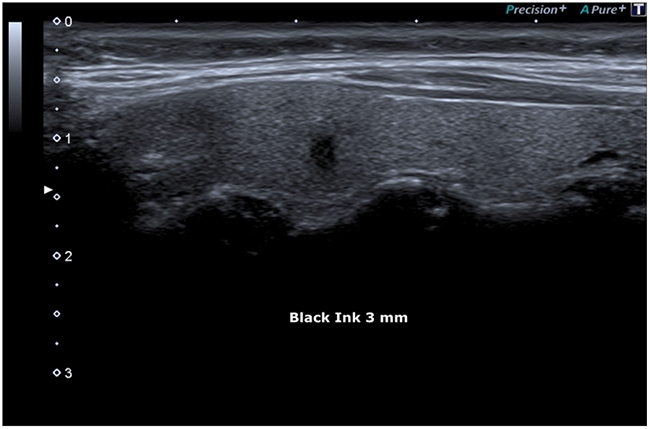

Figure 3: Black Ink.

Figure 4: Black Ink.

Figure 5: Black Ink, irregular margins: 3 mm.

The tumor characteristics of the “Black Ink”, highlighted in this case report, provides a reliable prognostic classification, in order to define an effective therapeutic plan.

Thyroid cancer is among the most common cancers in women. We described a case of a 58-year-old woman with a Ø 0.3 cm “Black Ink” image, which was subjected to FNAC and cytology examination and treated with total thyroidectomy with subsequent histology report of papillary thyroid microcarcinoma (invasive type). Ultrasonography together with FNAC have proven to be the most sensitive diagnostic imaging techniques for the early diagnosis of this thyroid neoplasm.

We are convinced that, despite the very small size of this micro-lesion, Black Ink echopattern represents a very important biological risk factors and that size, actually, has a serious consideration in malignancy assessment.